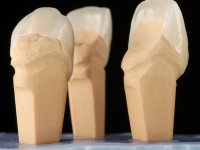

Realizado o diagnóstico e tomada a decisão quanto ao tratamento a executar, tornou-se importante definir qual a sequência de trabalho a adotar no sentido de conseguir a reabilitação da D.V.O. (V.D.O), de forma progressiva e equilibrada. Na primeira fase fez-se uma pré-impressão da arcada inferior com silicone tipo “putty” e em seguida realizou-se o preparo dentário de todo o sector posterior. O preparo para os overlays foi feito coronalmente à linha amelo cementaria no sentido de ser o mais conservador possível. A impressão foi feita com técnica de dupla mistura após afastamento gengival realizado com pasta de caulino. A provisória foi realizada com resina composta de polimerização dual. Em laboratório foram realizados os overlays após se ter aberto ligeiramente (1,5mm) a D.V.O. nos modelos montados em articulador semi-ajustável. Simultaneamente o sector antero-inferior foi encerado no sentido de acompanhar este aumento da D.V.O. Também foi confecionada uma chave de silicone translucido para posterior confeção dos provisórios antero-inferiores. Em boca foi primeiro realizada a provisionalização dos dentes anteriores utilizando resina composta previamente aquecida após preparação das superfícies dentárias para a adesão. Foi colocado o dique de borracha para promover o isolamento absoluto e posteriormente foram colados os overlays. Em laboratório foi realizada nova chave de silicone para confecionar os provisórios antero-superiores. Seguidamente em boca foram preparados os seis dentes antero-superiores após colocação do fio de afastamento gengival. Feita a preparação adequada das superfícies dentárias foi realizada a impressão com técnica de dupla mistura e a respetiva provisória. Em laboratório foram confecionadas 6 facetas feldespáticas num modelo de trabalho tipo “Geller”. A provisória foi removida e as facetas foram coladas em boca utilizando um isolamento relativo competente. Esta opção foi tomada em virtude de uma prévia experiencia negativa com a colocação do dique de borracha na mandibula. Após a colagem dos laminados antero-superiores foram dadas 12 semanas para avaliar a adaptação do paciente à nova situação e então iniciar a confeção das facetas antero-inferiores. Após colocação do fio de afastamento gengival. foram feitos os preparos dentários adequados e em seguida foi feita a impressão. Também foi feita a preparação do dente 3.4 que, entretanto, tinha sofrido uma fratura do overlay. As facetas e a restauração do 3.4 foram realizadas num modelo de trabalho tipo “Geller”. Após remoção da provisória, as facetas foram coladas em boca, utilizando um isolamento relativo pelas razões apontadas anteriormente. Após colocação do trabalho o paciente foi reabilitado por outros colegas com um implante na zona do 2.6 e substituição da coroa aparafusada sobre o implante colocado no local do 3.5. Posteriormente surgiram fraturas nos overlays dos dentes 4.7 e 3.7 que foram reabilitados com overlays em Zr.